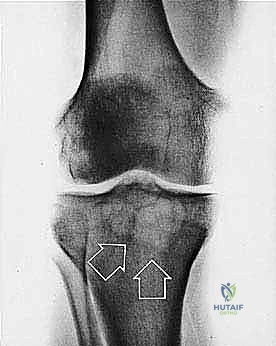

| حدود الورم في الأشعة | واضحة، محددة بدقة (Sclerotic margin) | غير واضحة، متآكلة (Moth-eaten appearance) |

| اختراق قشرة العظم | نادر جداً | شائع جداً، يمتد للأنسجة الرخوة المحيطة |

2. الموقع (Site - T): هل الورم داخل الحيز العظمي (Intracompartmental - T1) أم اخترق القشرة وخرج للحيز الخارجي (Extracompartmental - T2)؟